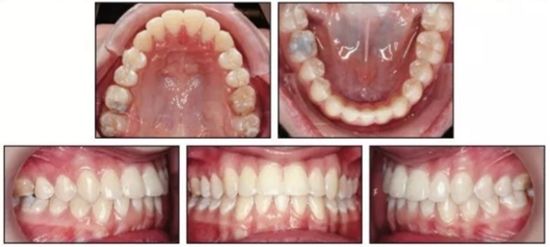

治療結(jié)束后,患者雙側(cè)達(dá)到安氏I類關(guān)系,正常的覆合覆蓋及接近理想的前牙軸傾度。頭側(cè)結(jié)果再次確認(rèn)了通過上頜伸長安氏III已得到矯正,SNA從73.1°增大到78.1°(表1)。上頜前磨牙間寬度增加了約9mm。下頜MP-PP角減小了4.9°,面型接近中等面型。

患者繼續(xù)佩戴活動保持器,治療后13月隨訪提示其仍處于一個穩(wěn)定的咬合關(guān)系。(圖5)